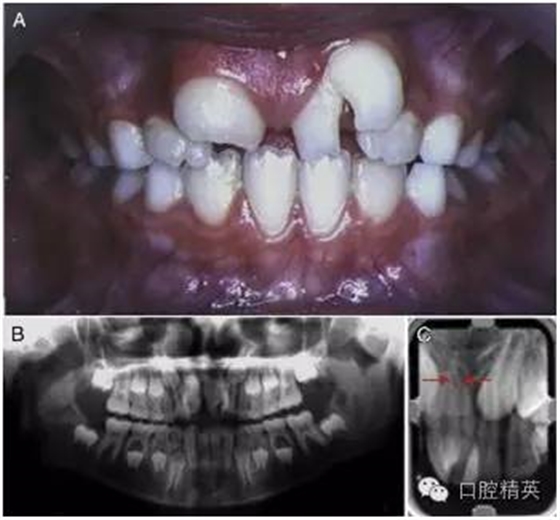

2002 年,一位左上中切牙巨大的 9 歲女孩因抱怨美觀問題而被轉(zhuǎn)診過來(圖 1)。經(jīng)初步檢查,患者口腔中剩余的其他乳牙與恒牙大小和形狀都表現(xiàn)正常,牙齒數(shù)量上無減少?;颊呒易迨放c既往病史不詳。

圖 1 左上巨牙癥術(shù)前資料。(A)口內(nèi)正面像。(B)x 線全景片。(C)根尖片,箭頭所指處表明兩顆牙齒的根管影像是分開的。

進(jìn)一步檢查發(fā)現(xiàn),一顆形狀不規(guī)則的多生牙與左上中切牙在冠部頸 1/3 處融合在了一起。然而,通過全景片與根尖片可以判斷出兩顆牙的根管影像是各自分開的 (圖 1-B,1-C[ 箭頭處])。這可以被認(rèn)為是一條垂直向的發(fā)育溝把牙冠從近中 1/3 處分成兩個(gè)錐形牙冠造成的并生。患牙牙冠近遠(yuǎn)中總寬度為 15mm,而正常的右上中切牙牙冠近遠(yuǎn)中寬度只有 10mm。

由此造成的切牙區(qū)域的擁擠導(dǎo)致了融合牙遠(yuǎn)中部分的唇傾(作為整體來描述則是遠(yuǎn)中頰側(cè)扭轉(zhuǎn))。對(duì)融合牙用冷測(cè)法進(jìn)行牙髓溫度測(cè)試,測(cè)試結(jié)果為正常。

根據(jù) x 線片,可以清楚地觀察到兩個(gè)明顯的牙根因融合的牙骨質(zhì)連在了一起。結(jié)合口內(nèi)臨床檢查可以確定,這是由一顆不規(guī)則的多生牙與左上中切牙融合在一起的融合牙。檢查過程中,未發(fā)現(xiàn)牙髓與根尖周組織存在其他的異常。